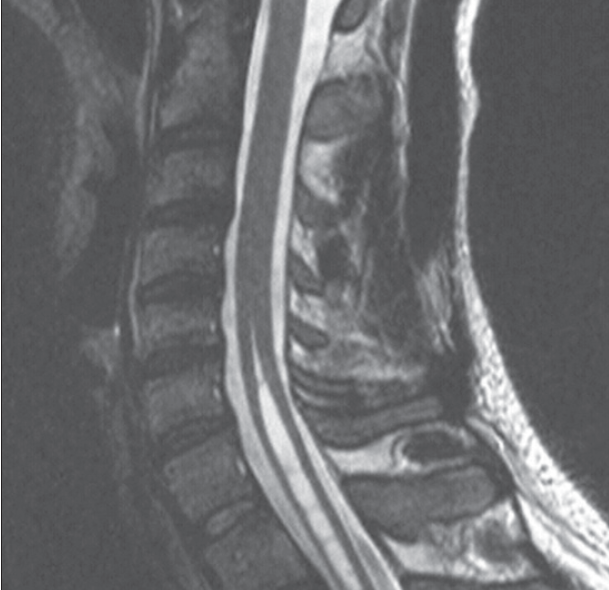

syringomyelia

10/12/2012

John Whyte, MD, MPH; Anthony L. Filly, MD

<p>A 37-year-old man presents to the emergency department (ED) with a headache that developed approximately 3 days earlier. The throbbing headache has worsened over the past few days...